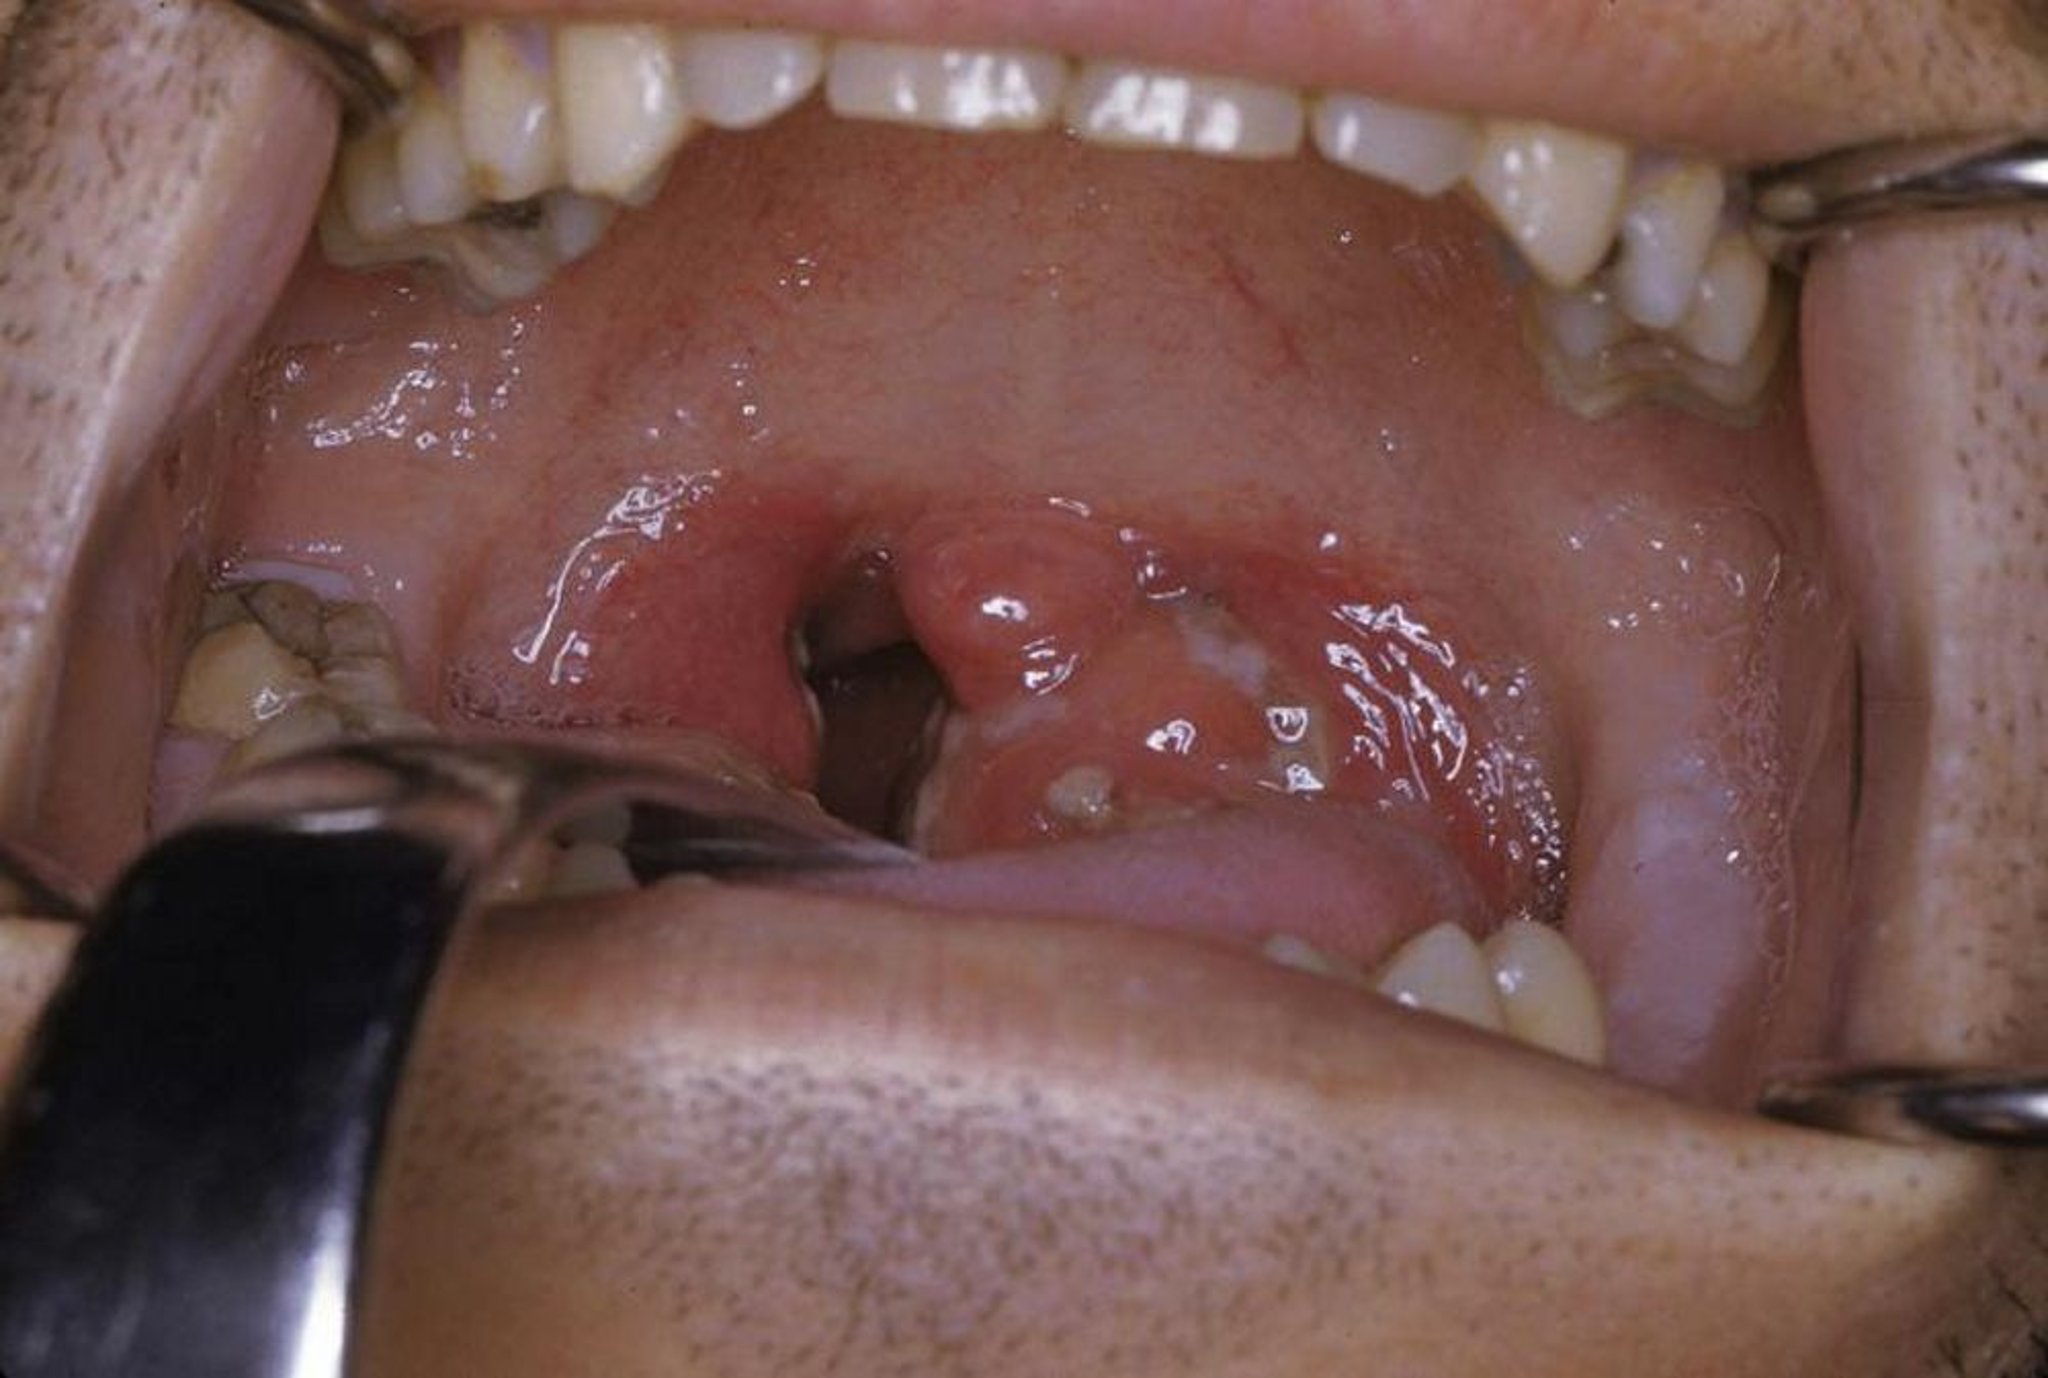

Esta fotografia muestra amigdalitis aguda con exudado y eritema.

Foto cortesía de Clarence T. Sasaki, MD.